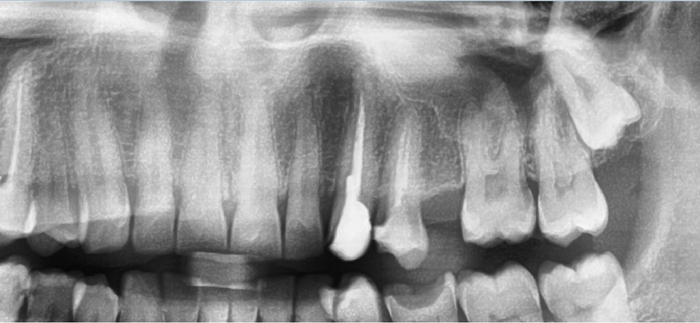

Весной 2021 лечил острый пульпит на 47 зубе, лечили каналы и депульпировали. Осенью поставил коронки на 45-47. В июле этого года сделал кт и врач сказал периодонтит и убыль кости на 46 и особенно на 47. Так понимаю 47 очень сложно вылечить будет. В клинике сказали, если не удастся вылечить, то только удалять. Имею ли я право по закону, если придется удалить 47 зуб, поставить в другой клинике имплант и потребовать с первой клиники компенсацию стоимости его установки ? Как правильно поступить?